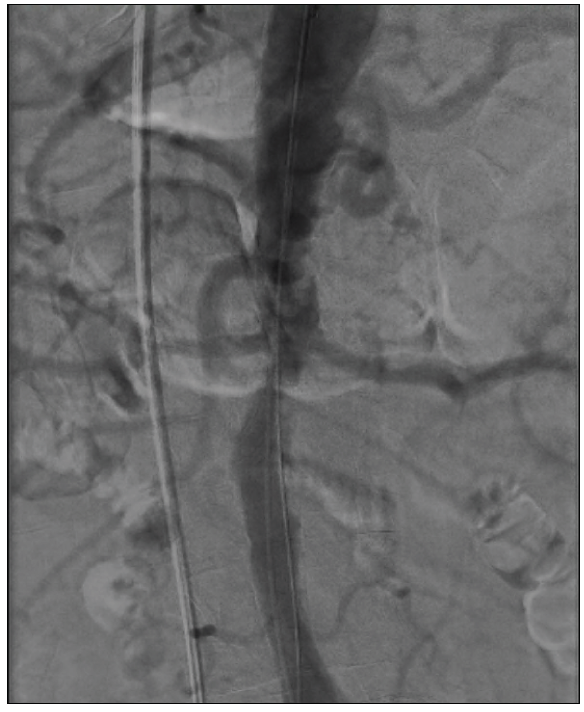

After an informed consent discussion with the patient, the decision was made to proceed with percutaneous revascularization of the RCA and LMCA lesions to achieve functional complete revascularization. Using a 6-F left radial approach, the RCA lesion was intervened on successfully with one drug-eluting stent deployed to the proximal vessel. Next, 7-F access was achieved in the right common femoral artery (CFA); however, difficulty was encountered with wire transit across the distal abdominal aorta. Aortoiliac angiography was performed, demonstrating severe stenosis at the level of the renal artery ostia (Figure 1). Carefully, a wire was manipulated across this lesion, and a long 7-F, 45-cm sheath was delivered.